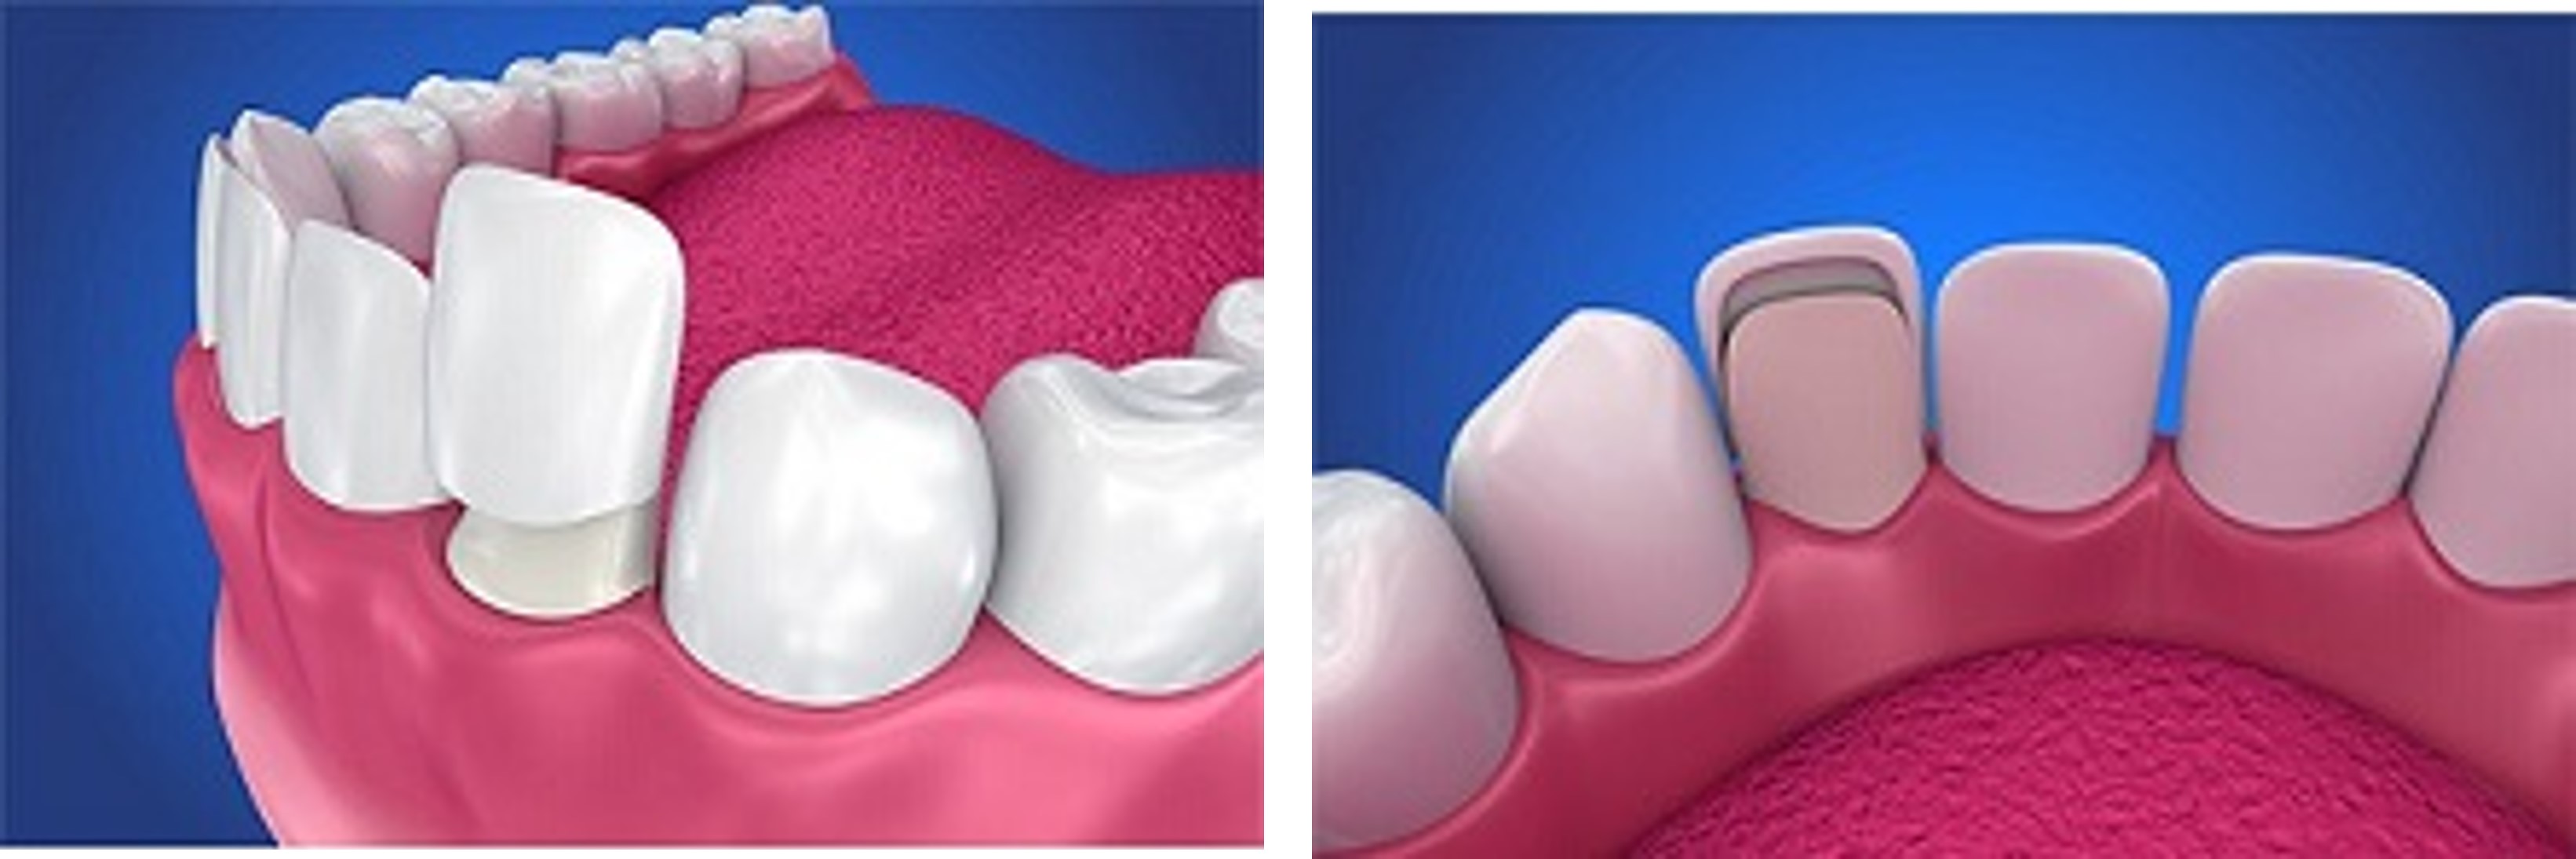

陶瓷貼面

牙齒貼片(有時稱為陶瓷貼片或牙科瓷貼)為薄薄的一片,主要用於改變牙齒的顏色、形狀、大小或長度,黏貼位置於覆蓋牙齒的表面以改善外觀。

材質可以由陶瓷或樹脂複合材料製成。陶瓷貼片比樹脂貼片更能抵抗污漬,更好模仿天然牙齒的光反射特性。